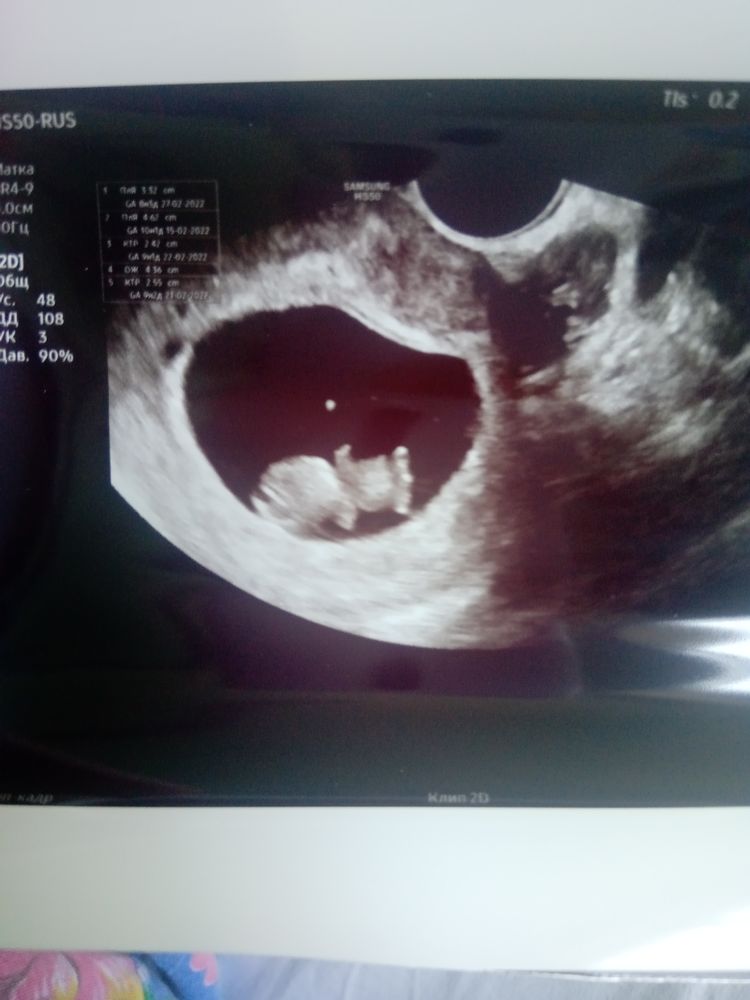

На этом сроке у них еще хвостик. Мне вот тоже сказали, что мальчик похоже. И то самое место типа, на фото хорошо видно. Изображение Ааа видите, мальчиков у нас нет))))

Twilight sparkle, эмбрион проходит стадию с хвостом, который потом остается рудиментом в организме - верно, копчиком. Изображение

Это не писюн, а половой бугорок ( предок члена и клитора) и в этом возрасте он у мальчика и девочки совершенно одинаковый- настолько, что даже, рассматривая эмбрион такого возраста глазами в упор, пол можно определить только генетически. Врач ваш, извините, так себе грамотный.

Именно в 9.5 недель ни один узист, даже супер гениальный не определит пол. Там даже угол наклона ещё не сформирован, по которому смотрят. Так что если и парень будет, это чисто пальцем в небо. Если только, конечно, у вас малыш не опережает развитие на 2.5-3 недели.